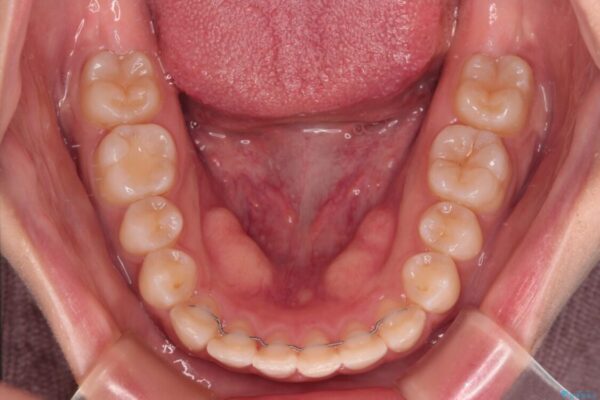

前歯のデコボコを気にして来院された患者様です。

治療後

• 【モニター】短期間で終わりたい ワイヤー装置での非抜歯矯正 治療後画像